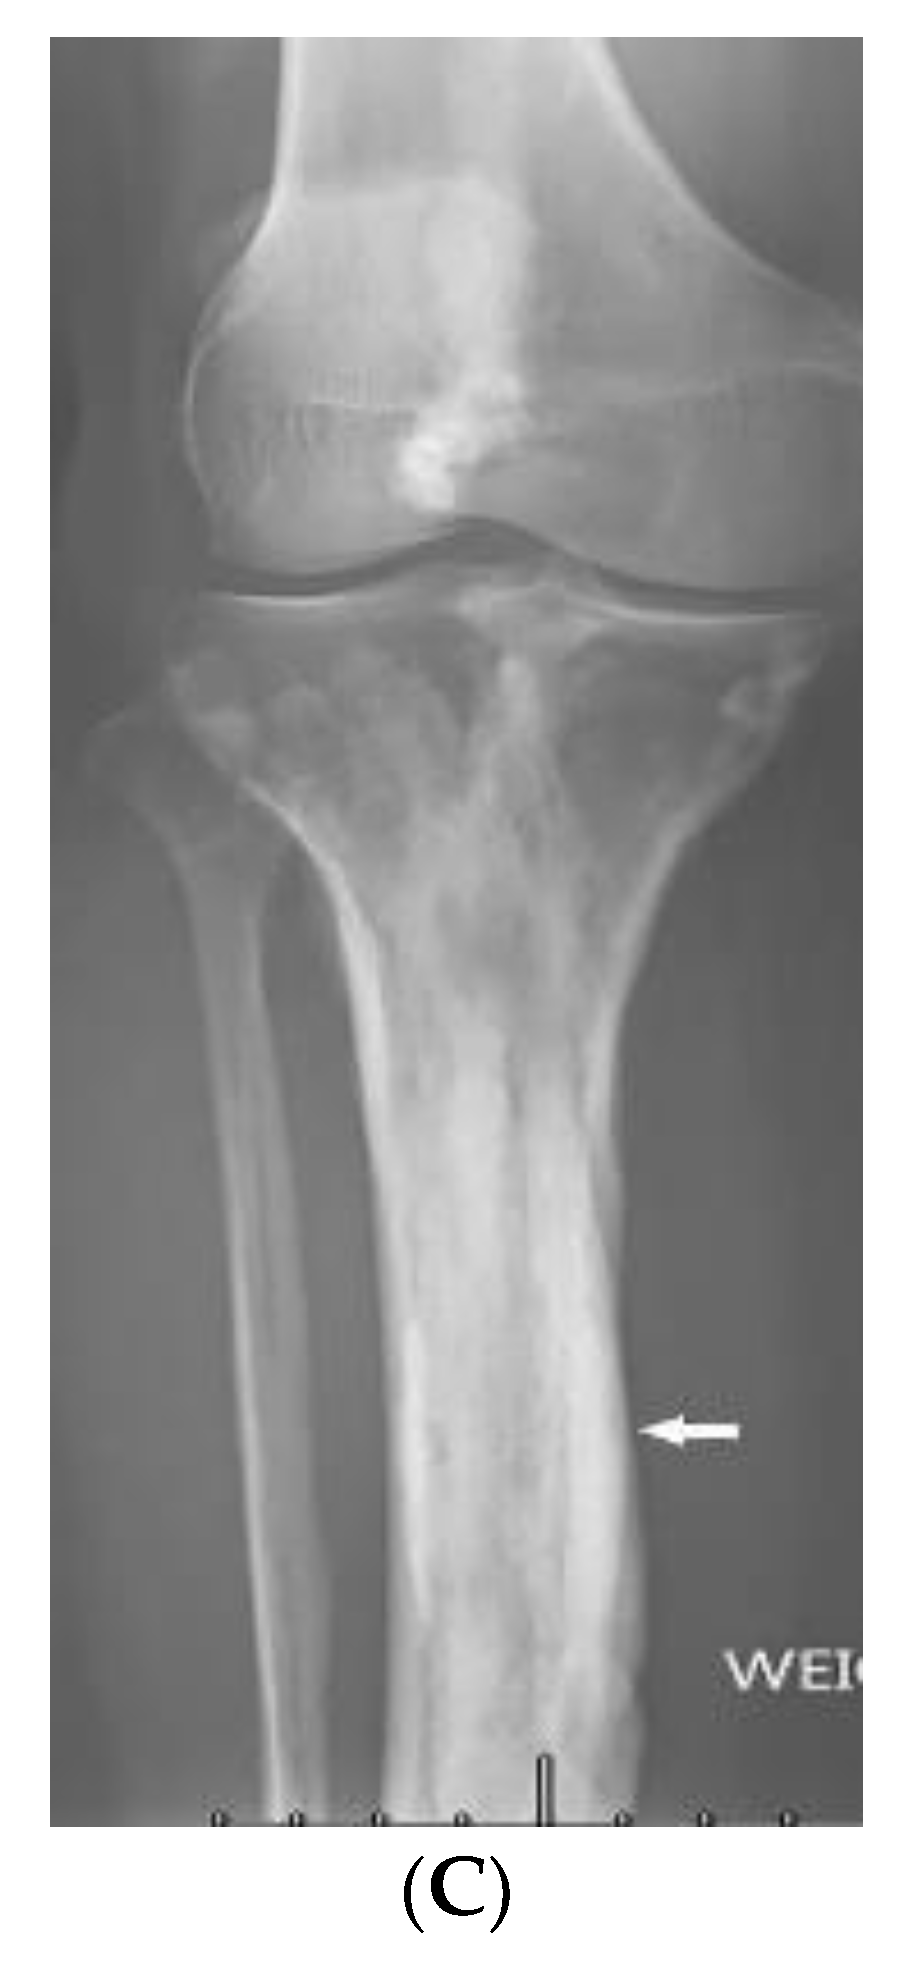

| Buschke–Ollendorff syndrome | Dermatofibrosis lenticularis disseminata Osteopoikilosis Melorheostosis | Bony islands and multiple sclerotic lesions cause mottled appearance Cortical thickening with undulating bone |